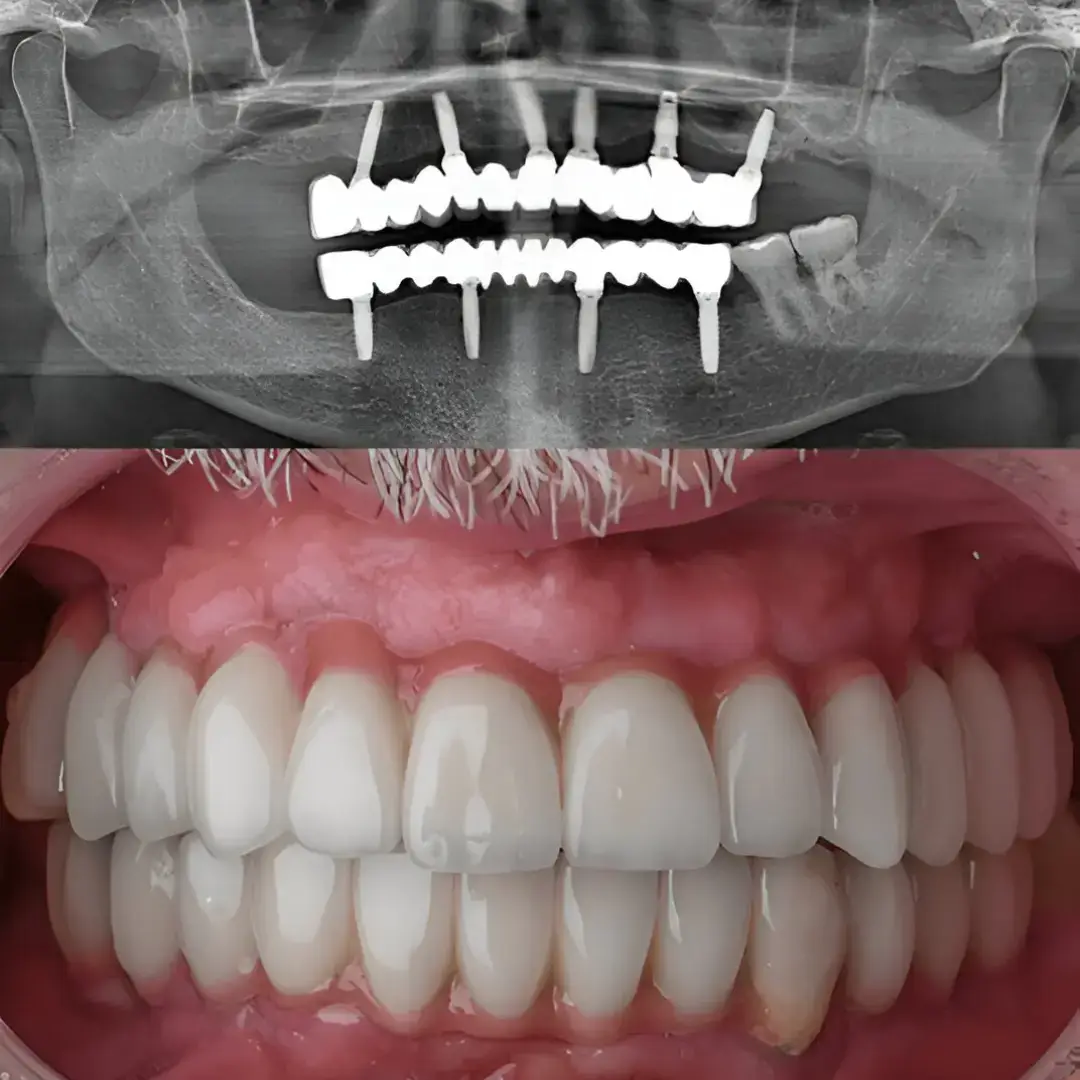

Dental implants offer a reliable and long-term solution for all the individuals who suffer tooth loss. These artificial tooth roots, made of biocompatible materials like titanium, are surgically fixed into the jawbone to support replacements such as crowns, bridges, or dentures.

Dental implants are prosthetic devices designed to mimic the natural structure of teeth. Surgically placed into the jawbone, they serve as a stable base for artificial teeth, like crowns and dentures.

Implant Placement

A titanium dental implant is surgically placed in your jawbone to serve as a support. The implant functions like a normal tooth and over time, integrates with the bone by a process called osseointegration.

Crown Adjustment

A custom-made crown is fitted onto the abutment. The crown acts as a natural tooth restoring the normal functionality and appearance of your teeth.